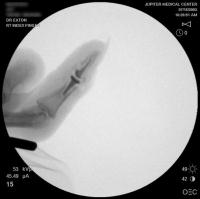

Intraoperative fluoroscopy.

Intraoperative fluoroscopy using the same technique as above. The trial spacers: